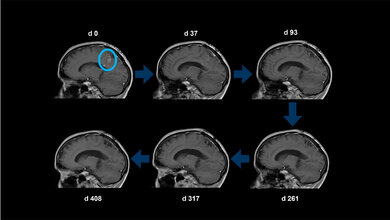

Bei keinem der Geimpften beobachteten die Ärztinnen und Ärzte schwerwiegende Nebenwirkungen. Fünf der acht behandelten Patienten entwickelten spezifische Immunantworten gegen das mutierte Protein, dabei stand die Aktivierung von CD4-T-Helferzellen im Vordergrund. Bei einer der Betroffenen, die eine starke Immunreaktion gezeigt hatte, bildete sich der Tumor komplett zurück, sie blieb für 31 Monate tumorfrei.